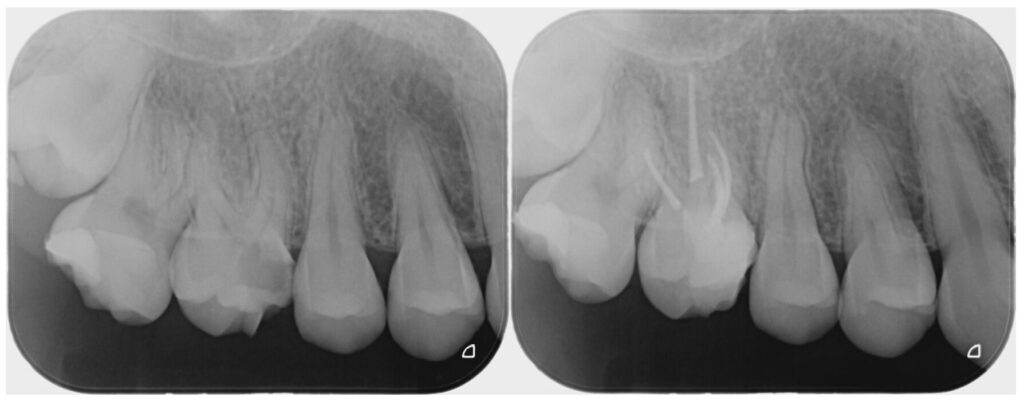

歯内療法専門医と連携して治療を行なった症例です。

虫歯と痛みが大きい部位に関しては、保険適応外の根管治療専門医が精密根管治療を行い、その後被せ物をジルコニアにて行いました。

| 精密根管治療後のジルコニアセラミック(20代女性) |

| 精密根管治療後、ジルコニアセラミックによる補綴修復を行なった。 |